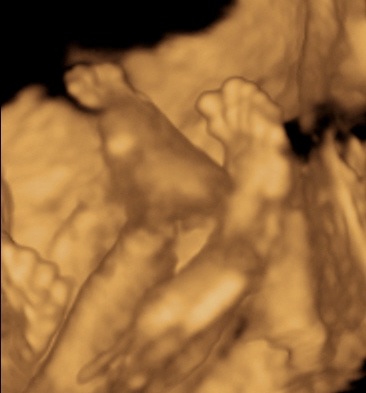

A 3D-s babafotok meg mindig lenyugoznek, nem birok betelni veluk. SZomoruan olvasom, hogy mennyi aprobb-nagyobb kellemetlensegetek van, de szerintem mindenki nagyon szuperul halad, ugyesek vagytok...le a kalappal foleg a dolgozok, vagy mar babasok elott! majd most teszek fel kepeket es is Azzurrarol, bar mar tobb, mint 5 hete keszultek, de ujabbak mar nem lesznek, es mivel kimaradtam abban az idoszakban, most potolom. Az tuti, hogy ezentul mindenkinek javasolni fogom a 4D-t ilyen koran is (22+1 hetesen voltunk), mert bar csimota ducibb volt az atlagnal es mar akkor volt rajta jo adagnyi izom (ez is a napi 1 l tej

), de egy sovanyabb baba is csodaszep szerintem...mindent el lehet mondani, csak azt nem, hogy csontkollekciok lennenek. Osszessegeben ugy nez ki, hogy ram hasonlit, de a szemoldokcsontja es a szaja az egy az egyben a parome...szerencsere...neki az sokkal szebb...remelem, haj-ugyben is ra ut majd